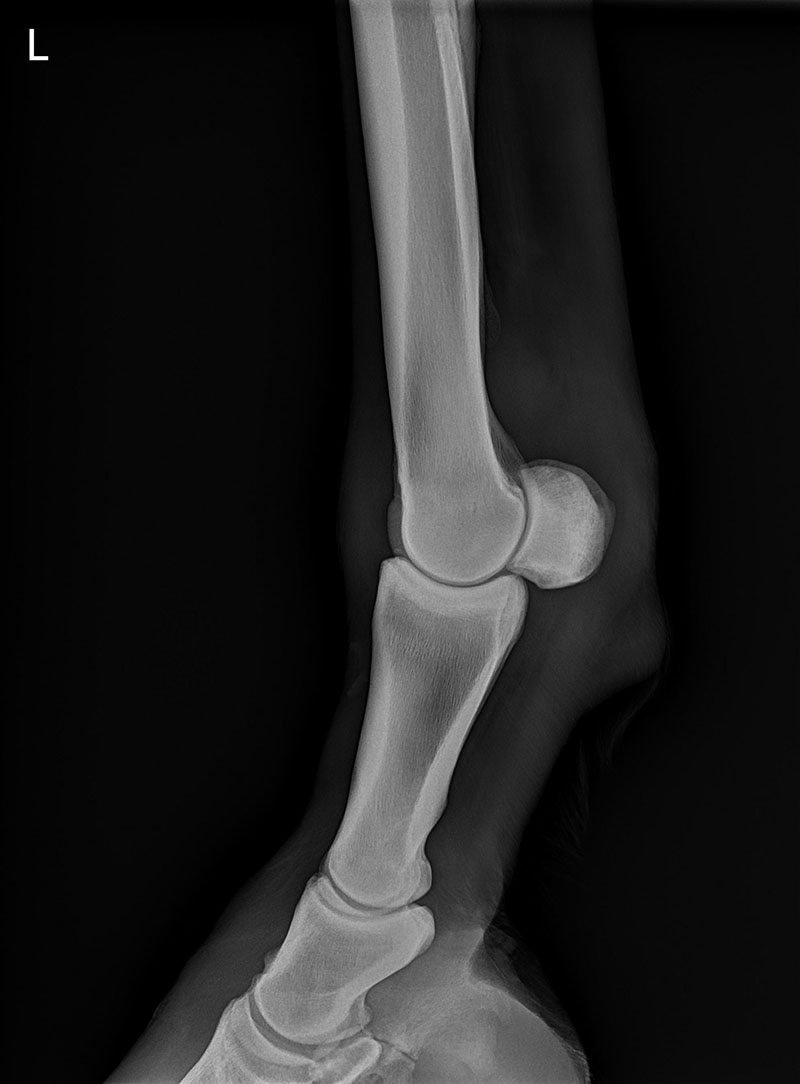

Radiography:

In the hospital, we have a dedicated x-ray suite in the hospital, which includes a large overhead gantry generator to penetrate through thicker areas, allowing us to get excellent imaging of the neck and back.

We have multiple wireless digital radiography (DR) systems as well as a wireless x-ray generator unit, which are available to go out on ambulatory calls.